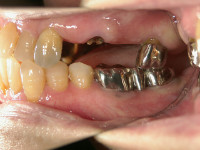

縫合後、インプラント違和感などがないことを確認し、アバットメント(土台)を装着します。

最後にクラウンを装着して、これでインプラント治療は終了となります(かぶせ物)。